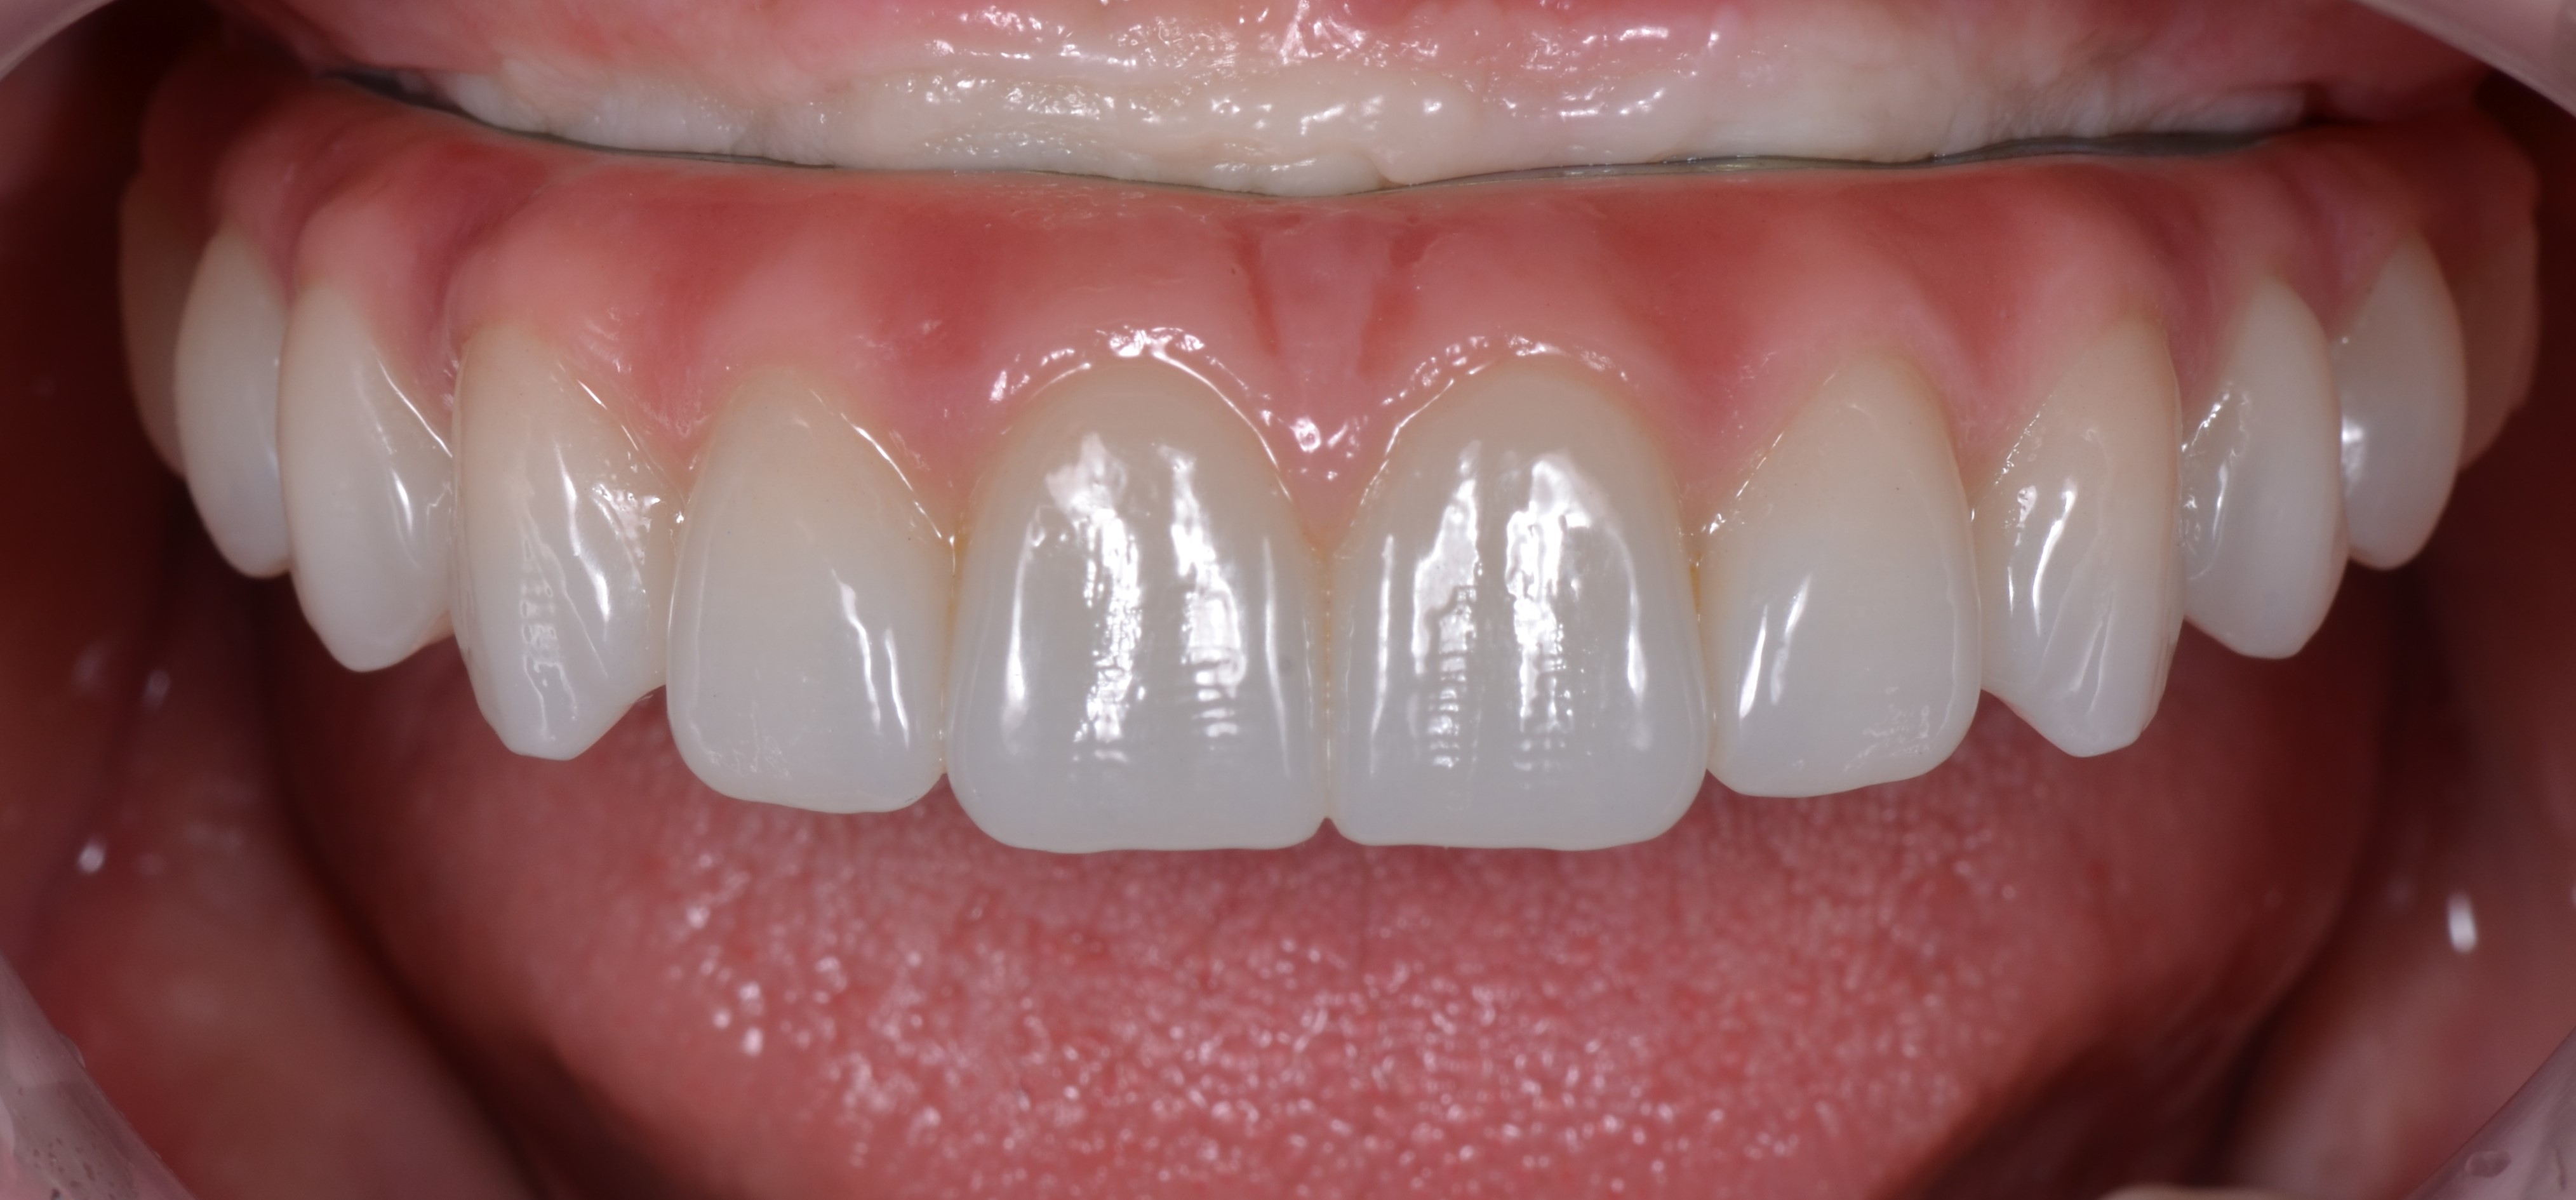

Через 8 месяцев после имплантации была зафиксирована несъёмная мостовидная керамическая конструкция с титановым каркасом по методике «All – on – 4» (рис. 46).

Благодаря междисциплинарному подходу при реабилитации стоматологических пациентов и богатому опыту нашей команды, нам удалось полноценно восстановить зубной ряд не только с эстетической точки зрения а, также восстановить его все функциональные параметры (рис. 47, 48,49).